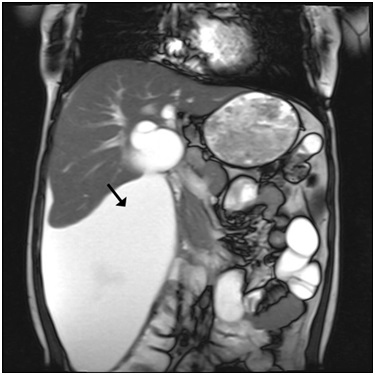

Figure 2: Abdominal MRI. There is a loculated fluid collection extending from the subcapsular region of the right hepatic lobe to the pelvic inlet, measuring approximately 25×12×14 cm.

figure 2